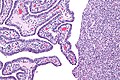

Cross section of a Fallopian tube with decidualization. H&E stain. (WC/euthman)

Normal uterine tube

Architecture:

- Finger-like projections into the lumen.

Cells:

- Ciliated cell.

- Columnar.

- Eosinophilic cytoplasm.

- Non-ciliated cell (AKA Peg cell).

- Nucleus more luminal.

- Nuclei stick-out like a golf tee.

- Secretory cells. (???)

- Basal cells, fried egg-like.